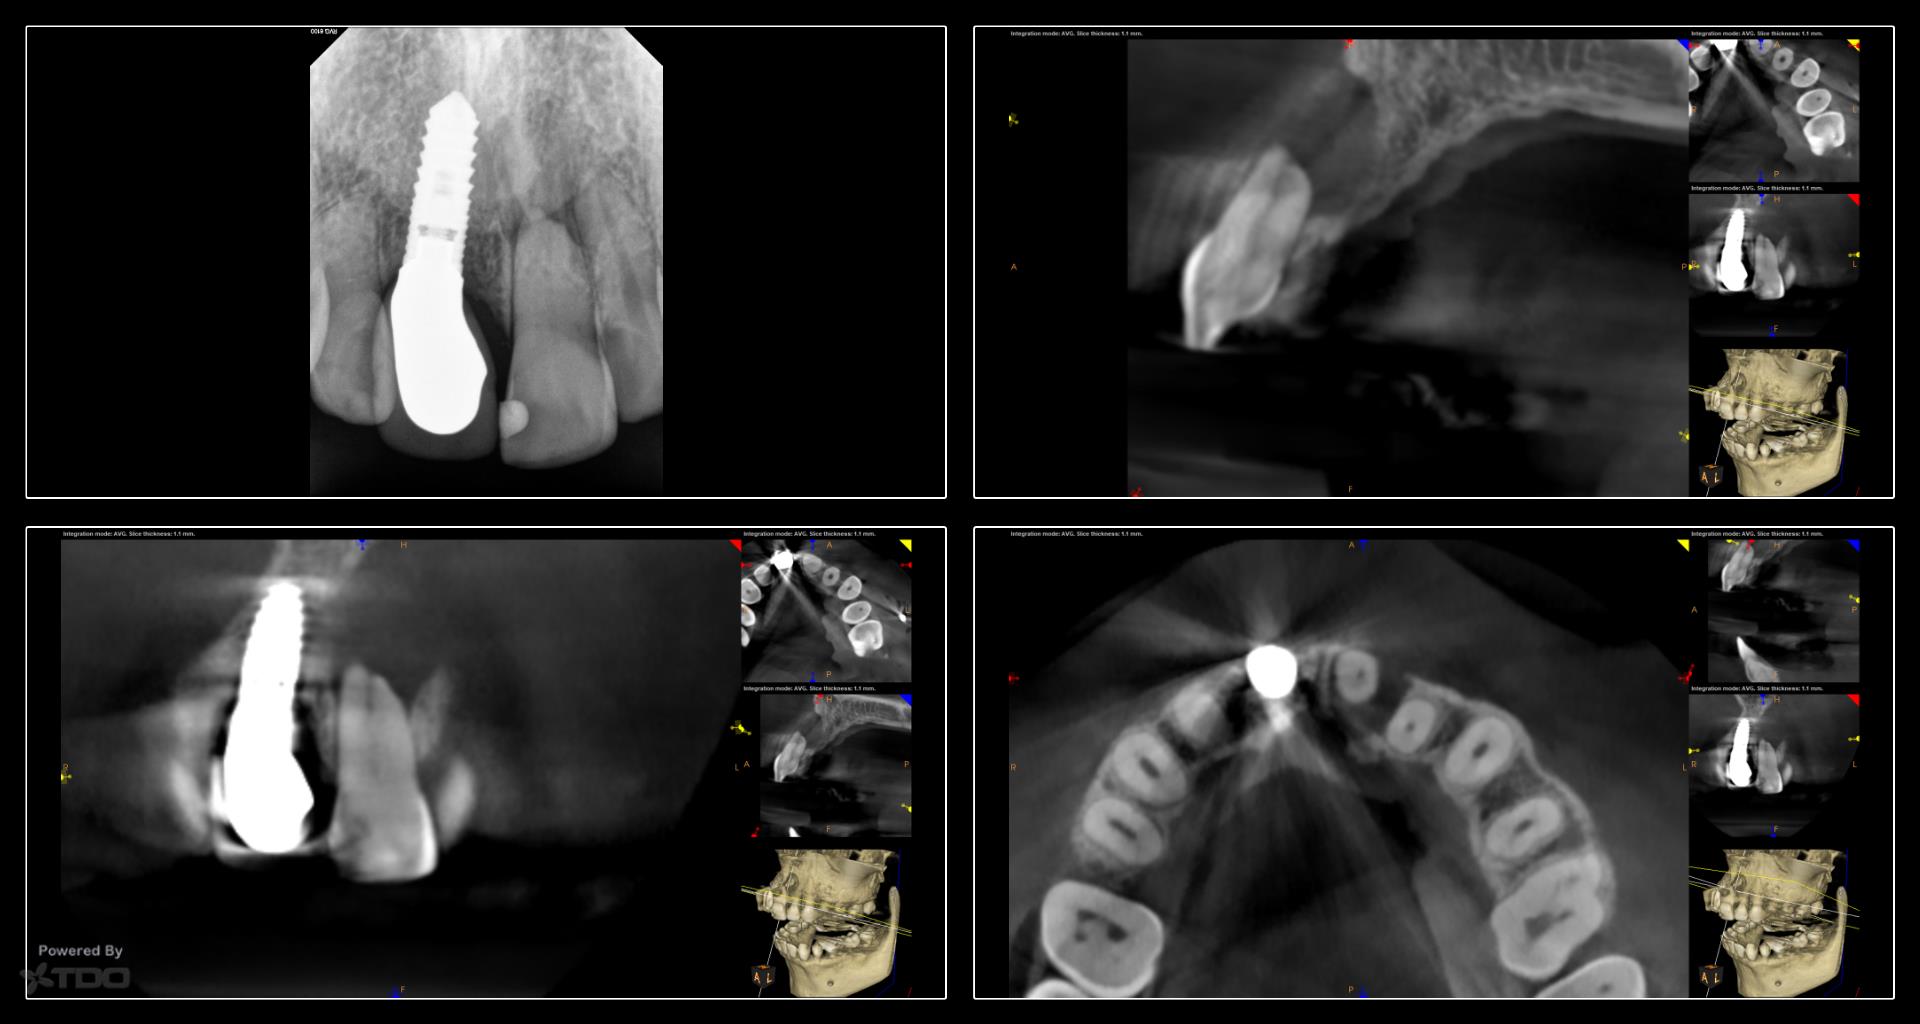

Collage-232629-Page00

This case was started in February and completed on Monday. We are currently bleaching the tooth. The buccal plate has regenerated rather nicely and the finding is continuing to heal. -Charles